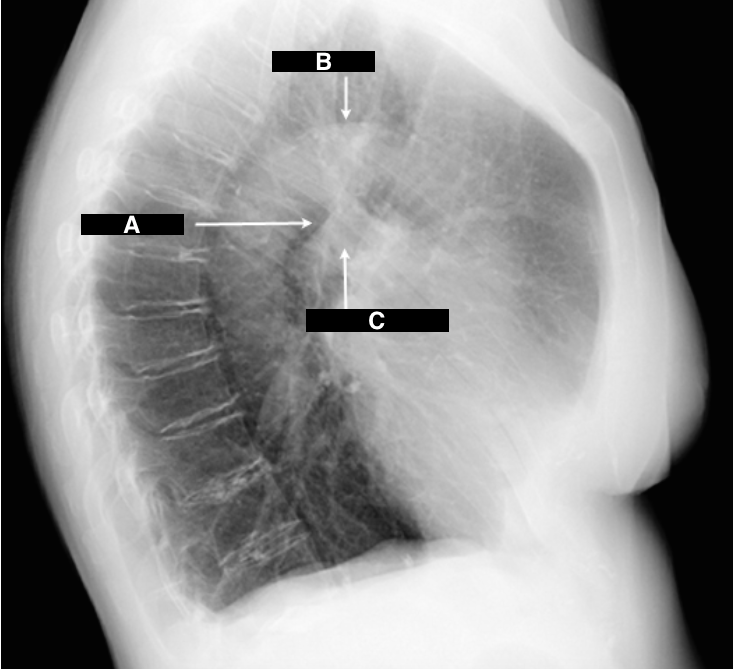

Identify A, B, C

A

A - AP Window

B - Aortic Arch

C - Pulmonic Arch